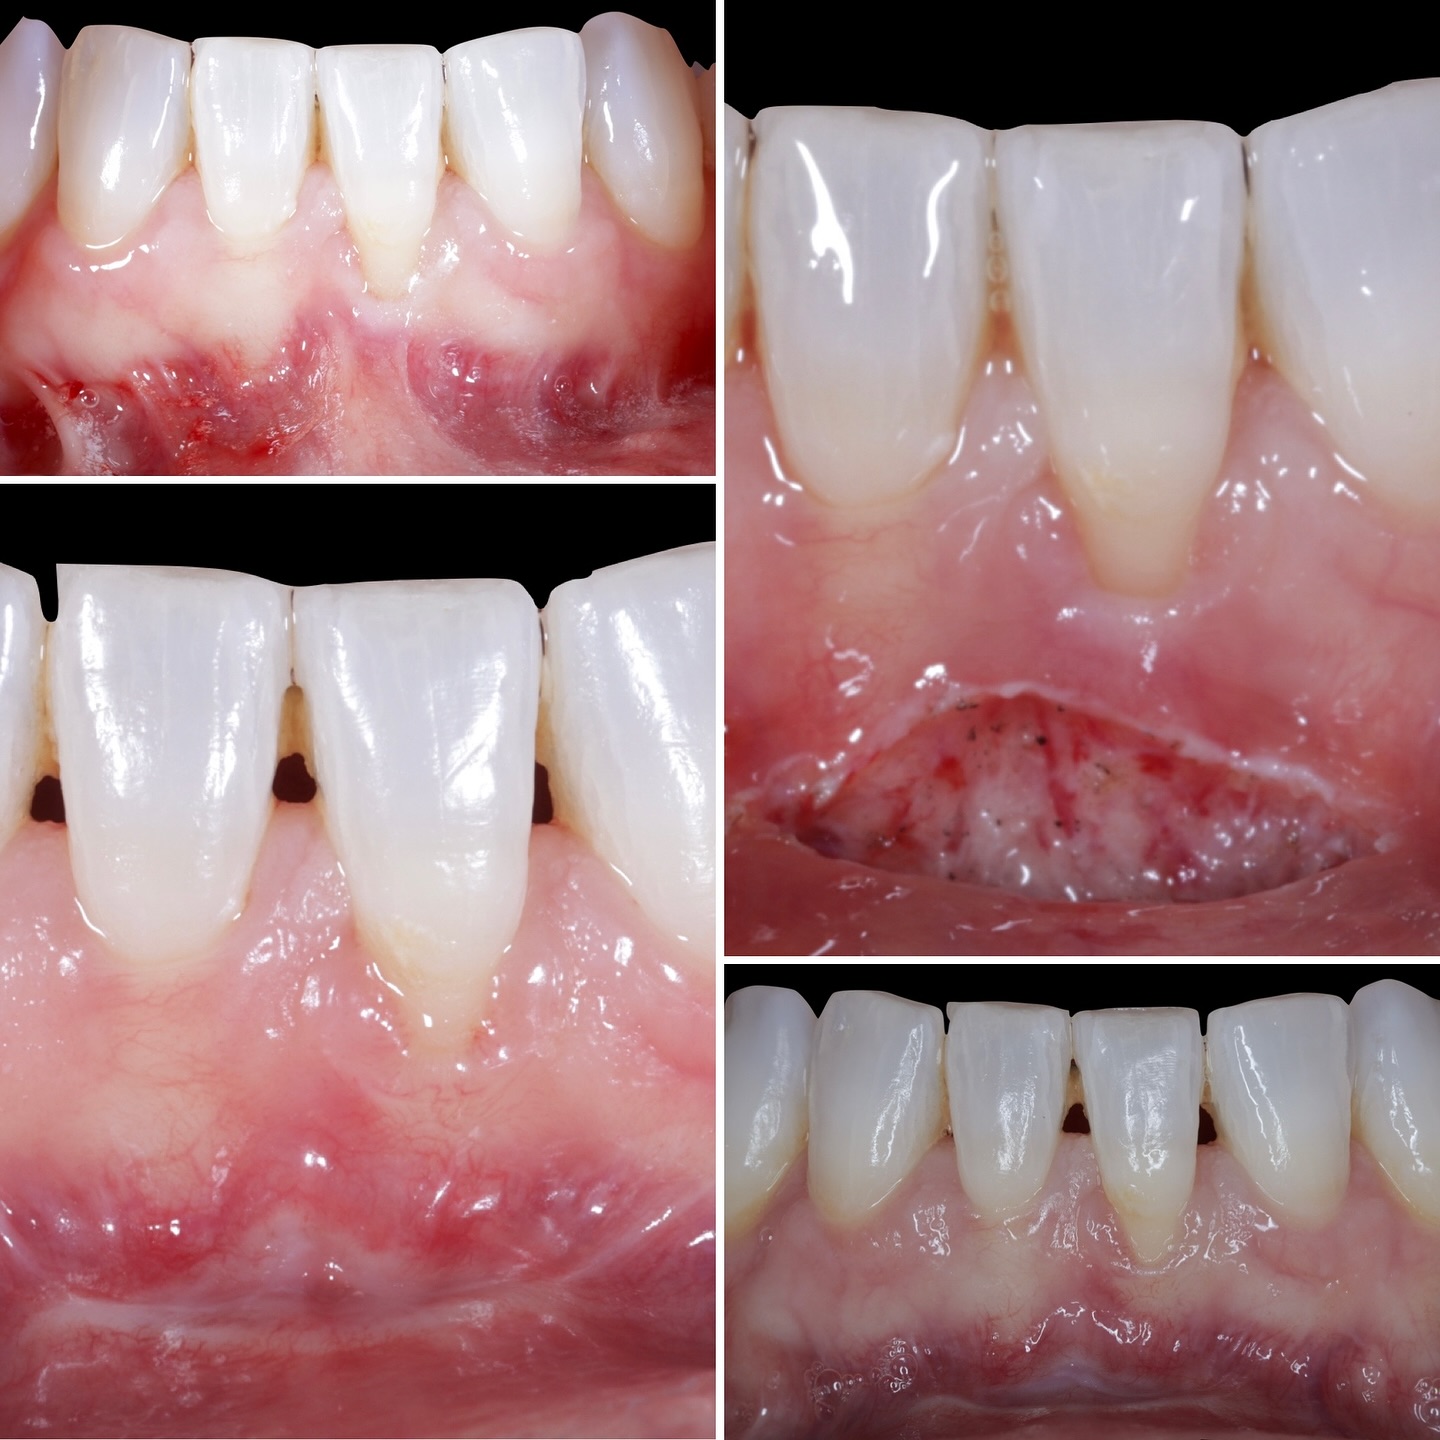

Durante una mañana, asistirás a una Cirugía Mucogingival de recubrimiento radicular de recesiones múltiples en IV y V sextante (36 a 43).

Gracias al uso del microscopio y a la proyección en tiempo real en pantalla, verás exactamente lo mismo que veo yo durante la cirugía, sin tener que estar

Podrás asistir a la planificación de casos y cirugía de injerto de tejido conectivo. Factores determinantes y elección de la técnica adecuada. Sumérgete en un protocolo predecible y técnicamente correcto para obtener resultados óptimos.

Aprende la planificación y técnica de la cirugía Mucogingival para el recubrimiento de recesiones y aumento de banda queratinizada en el sector anteroinferior

La formación comenzará con la presentación del caso clínico que se abordará durante el curso, seguida de una cirugía en directo, que permitirá observar paso a paso el procedimiento y la toma de decisiones clínicas. Durante la jornada se profundizará en los conceptos biológicos aplicados a

Durante una mañana, asistirás a una Cirugía Mucogingival de recubrimiento radicular de una recesión unitaria en 31 con frenillo asociado. Gracias al uso del microscopio y a la proyección en tiempo real en pantalla, verás exactamente lo mismo que veo yo durante la cirugía, sin tener que estar

Una estancia clínica pensada para quienes quieran iniciarse o dar un paso más en el campo de la cirugía mucogingival. Durante esta experiencia tendrás la oportunidad de aprender en directo cómo se planifica y se lleva a cabo una cirugía mucogingival mediante técnica de Túnel.

Formación teórico-práctica completa sobre las técnicas más avanzadas en cirugía mucogingival. Durante dos días intensivos, los participantes aprenderán desde la evidencia científica y la anatomía de las zonas donantes hasta la ejecución de injertos, cubrimiento radicular y aumento de

Dos cirugías mucogingivales en directo.